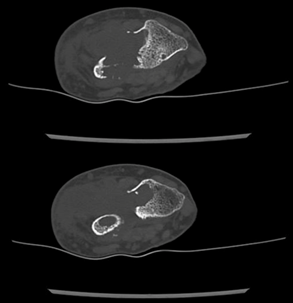

Posteriormente, consultó en el servicio de urgencias del hospital Carlos Van Buren de Valparaíso por exacerbación del dolor, constatándose aumento de volumen de muñeca y antebrazo izquierdo (Figura 1), razón por la que se le realizó una radiografía que evidenció lesiones líticas a nivel de epífisis distal del cúbito y parte del radio (Figura 2). Se sospechó un tumor óseo, por lo que se decidió hospitalizarla para complementar el estudio con una tomografía computada (TAC) de la muñeca, que confirmó los hallazgos radiológicos (Figura 3). Además, se le realizó un TAC de tórax, abdomen y pelvis, que evidenció adenopatías axilares izquierdas de aspecto secundario, sin otras lesiones sugerentes de metástasis o lesión sospechosa neoplásica primaria. Se solicitó un cintigrama óseo que evidenció aumento de la actividad osteoclástica intensa en el extremo distal del cúbito y radio izquierdo.

Figura 2 Radiografía de muñeca izquierda, proyecciones anteroposterior y lateral. Se evidencia lesiones osteolíticas del extremo distal del cúbito y parte distal del radio.